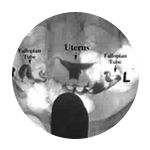

By looking at things like your health, medical history and lifestyle, our female fertility tests for women allow us to assess your individual situation and, if needed, decide on the best way to help.

During your assessment, we'll evaluate the following :